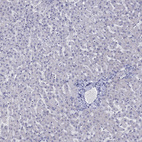

Immunohistochemistry analysis in human small intestine and liver tissues using HPA040591 antibody. Corresponding HTR4 RNA-seq data are presented for the same tissues.